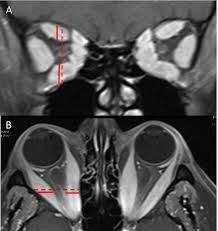

imaging findings in IIH

partially empty sella

optic nerve tortuosity, dilated optic nerve sheaths, visible protrusion of optic head into eyeballs

stenosis of transverse sinus